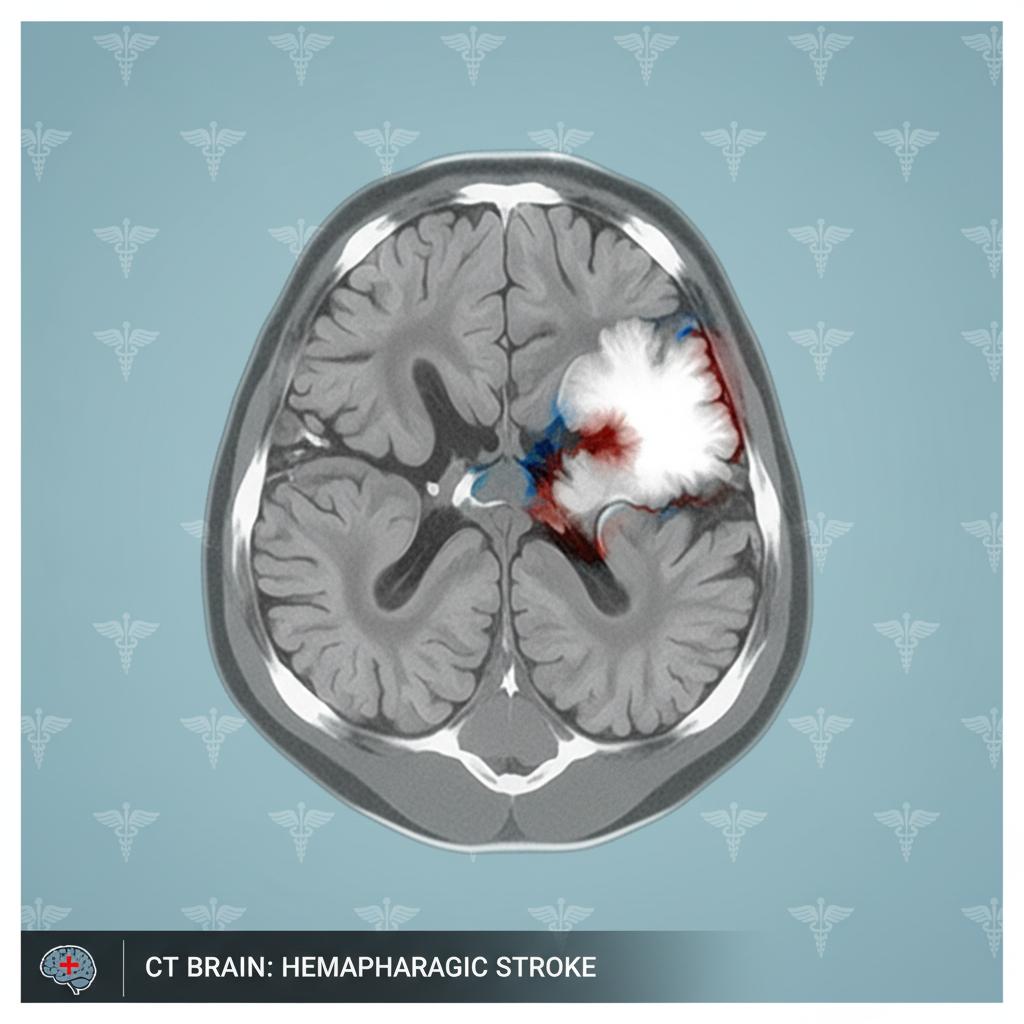

Wyobraź sobie, że twój mózg – genialny komputer, który steruje każdym oddechem i myślą – nagle zalewa się własną krwią. Nie ma tu miejsca na metafory. Udar krwotoczny to pęknięcie naczynia krwionośnego w mózgu, przez które krew dosłownie wylewa się do tkanki nerwowej. Powstaje krwiak, który rośnie, uciska neurony i niszczy ich połączenia. Każda sekunda to gra o życie: wzrasta ciśnienie, pojawia się obrzęk, mózg przestaje pracować normalnie. Brutalne? Tak. Ale właśnie tak działa ta „bomba z opóźnionym zapłonem”.

To nagłe pęknięcie naczynia krwionośnego w mózgu, skutkujące wylaniem się krwi do tkanki nerwowej. Wyróżnia się dwa główne typy: krwotok śródmózgowy i podpajęczynówkowy.

Skupisko krwi w mózgu powstałe na skutek pęknięcia naczynia – prowadzi do wzrostu ciśnienia i uszkodzenia komórek.

Kiedy krew wylewa się do mózgu, rozpoczyna się reakcja łańcuchowa. Krwiak uciska zdrową tkankę, zaburza przepływ tlenu i prowadzi do masywnej śmierci neuronów. Wzrost ciśnienia śródczaszkowego powoduje obrzęk – nie tylko w miejscu krwotoku, ale też w sąsiednich obszarach. Każda minuta oznacza utratę bezpowrotną milionów komórek nerwowych.